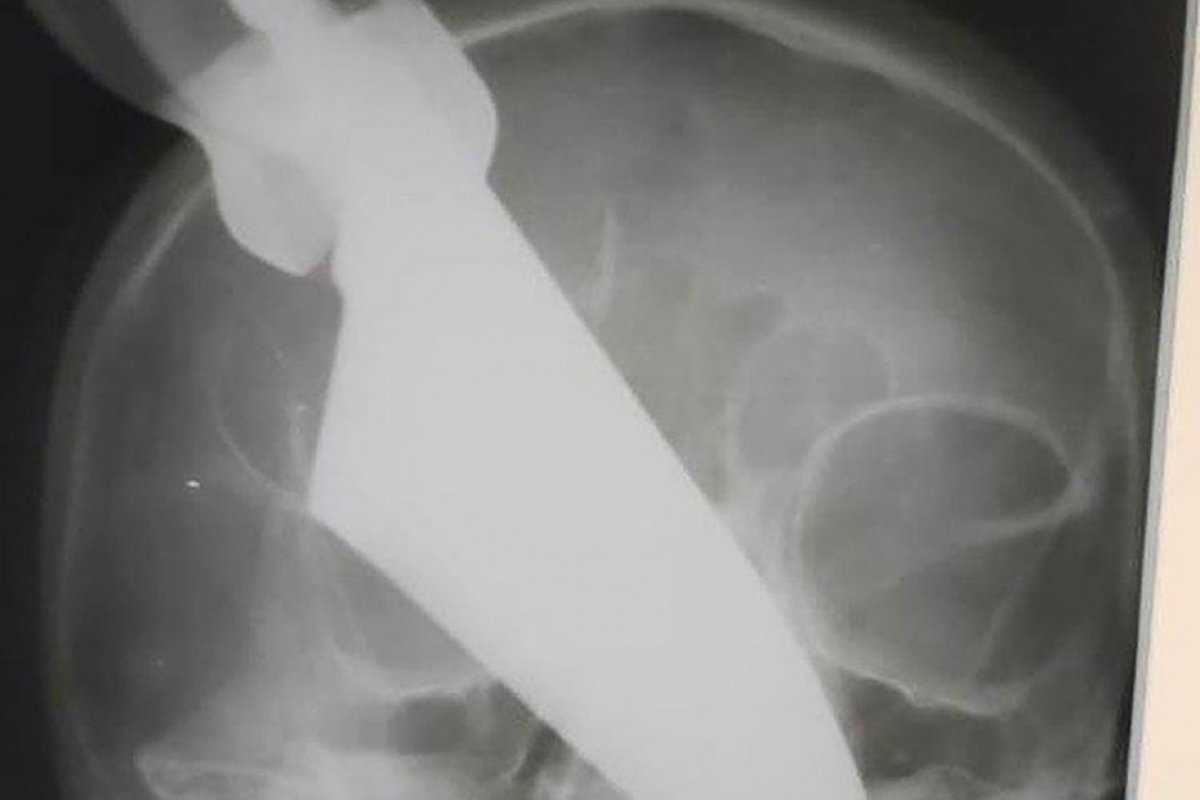

Uma mulher, que não foi identificada e que vive na região de Krasnodar, na Rússia, sobreviveu a um ataque do marido. Segundo a publicação do NY Post, ele enfiou uma faca de 25 cm em seu rosto, atingindo parte de seu nariz.

Depois de ser esfaqueada, a mulher, de 60 anos, correu para buscar a ajuda de seus vizinhos. Ela foi levada às pressas para um hospital, onde foi submetida a uma cirurgia para remover o objeto da face. A vítima terá que passar por tratamento para reconstruir o nariz e seios da face que foram os mais prejudicados pelo ataque.